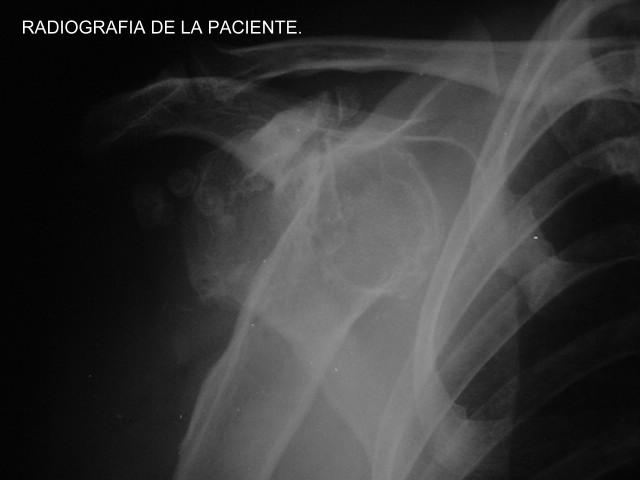

SECUELA DE TRAUMA HOMBRO DERECHO